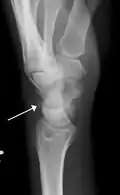

Triquetral fractures can occur due to forceful flexion of the wrist, causing an avulsion of the dorsal aspect of the bone that is often hidden on anterior radiographs, but can be seen as a tiny bone fragment on lateral views.